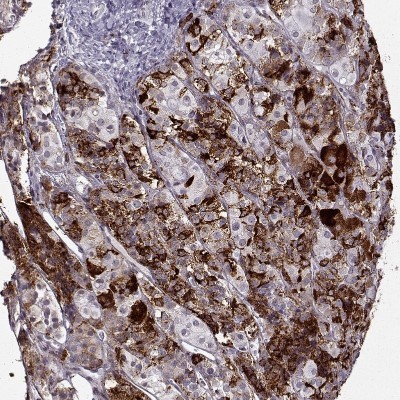

- Experimental details

- Immunohistochemistry-Paraffin: VGF Antibody [NBP2-31596] - Staining of human prostate shows no positivity in glandular cells as expected.